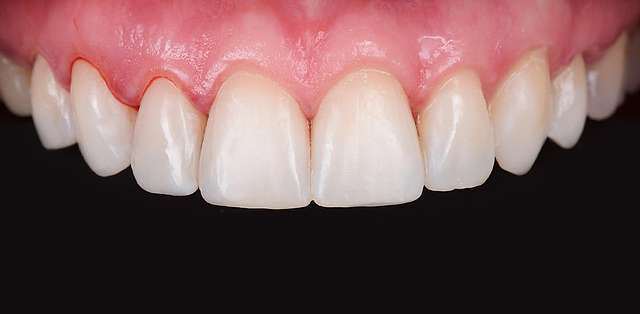

Here we had to deal with a significantly deviated midline, needed to bring one canine on the arch and basically realign teeth on both arches. To finish we did some composite details. When existing teeth have naturally beautiful shapes, orthodontics is many times a superior alternative to prosthetic treatment. It has one disadvantage: requires more time.